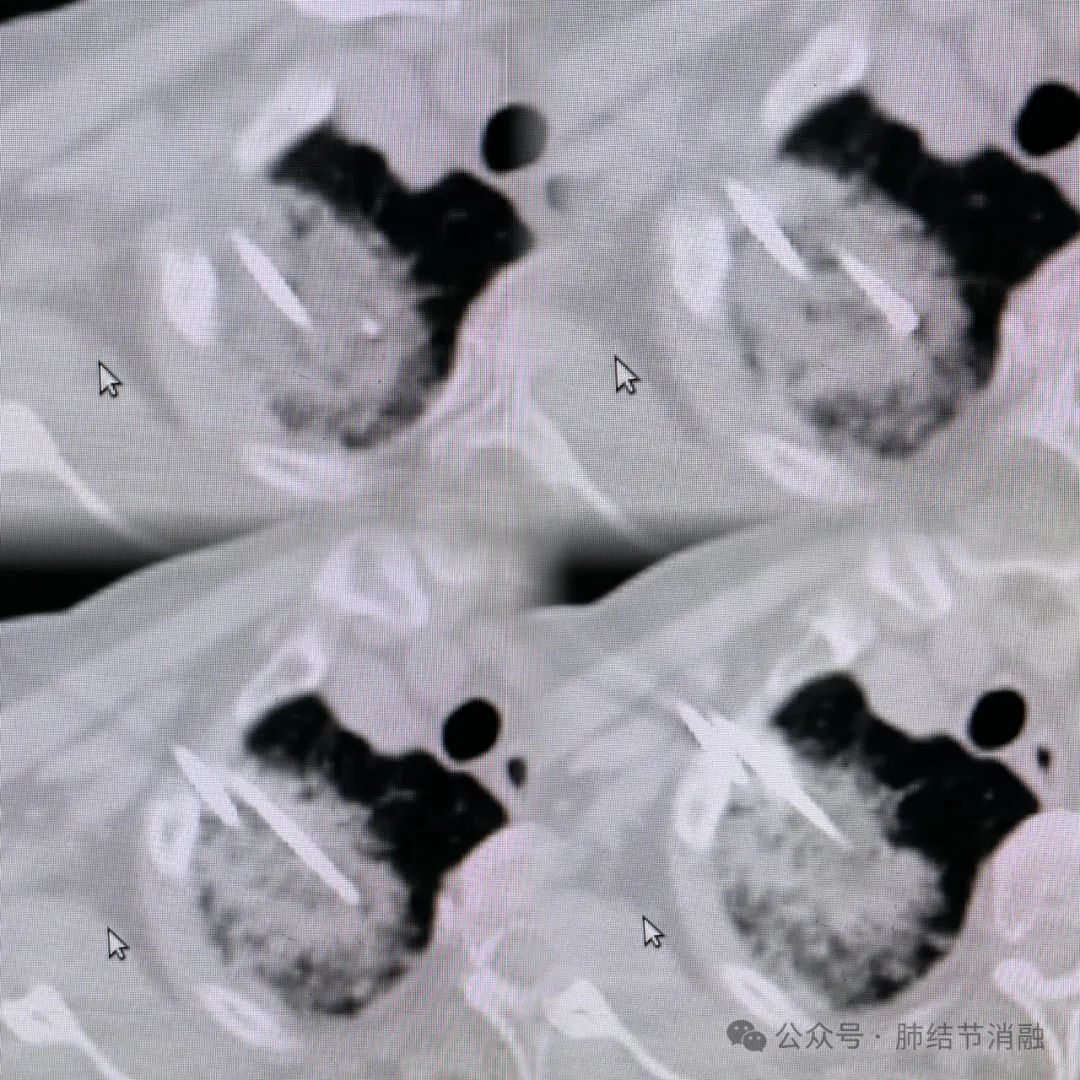

患者病灶位置高,位于第一肋间,病灶又比较大,需2根冷冻针联合布针消融。操作空间比较小,下面是我们双针交叉布针的实图。

布针结束后,给予三循环冷冻消融治疗,术中消融带已完全覆盖病灶,达到技术成功。